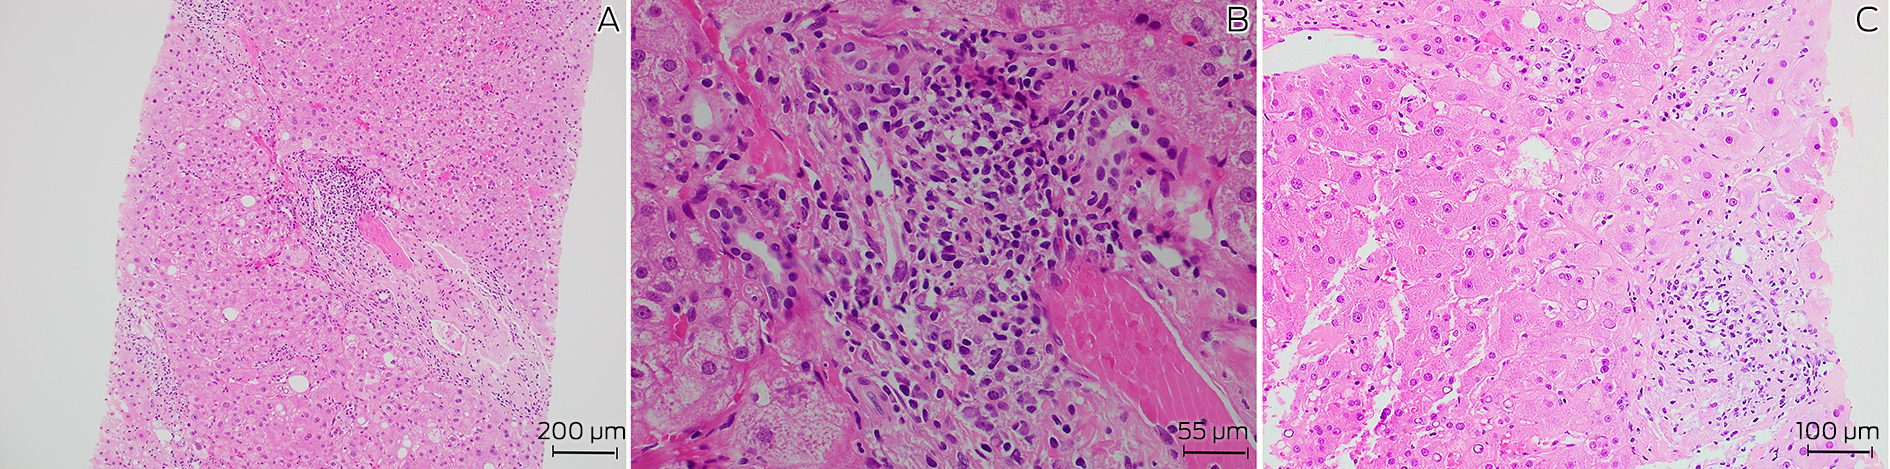

A 72‐year‐old man with a history of well controlled type 2 diabetes was admitted to a tertiary metropolitan hospital for investigation of fevers, night sweats and unintentional weight loss of 18 kg over six months. He had pancytopenia with no symptoms or signs to suggest a focal infection, malignancy or rheumatological disease. Prior outpatient investigation findings revealed mild splenomegaly, with a normal bone marrow aspirate and positron emission tomography scan. At its nadir, the haemoglobin level was 106 g/L (reference interval [RI], 125–175 g/L), white cell count 1.9 × 109/L (RI, 4.0–11.0 × 109/L), neutrophil count 1.2 × 109/L (RI, 2.00–8.00 × 109/L) and platelets 120 × 109/L (RI, 150–450 × 109/L). Notably, liver function test results were mildly elevated in a mixed pattern with alkaline phosphatase 138 U/L (RI, 30–110 U/L), γ‐glutamyl transferase 605 U/L (RI, 5–50 U/L) and alanine aminotransferase 78 U/L (RI, 5–40 U/L), with associated antinuclear antibody titre of more than 1280 (RI, < 160), and an elevated immunoglobulin G level of 38.6 g/L (RI, 7.5–15.6 g/L). Pertinent negative results included negative human immunodeficiency virus (HIV) and viral hepatitis serology, and negative anti‐smooth muscle and anti‐liver–kidney microsomal antibodies. Given these findings and the ongoing diagnostic dilemma, a liver biopsy was performed, showing mild interface hepatitis and lymphoplasmacytic infiltrate in the portal tracts (Box 1), and leading to a probable diagnosis of autoimmune hepatitis. Administration of azathioprine 25 mg and prednisolone 40 mg daily was initiated and the patient was discharged following improvement of his liver function test results.

Box 1 – Histopathology of liver biopsy showing (A) chronic inflammation and fibrosis of a portal tract (hematoxylin and eosin staining, 100 × magnification), (B) prominent plasma cells in portal tracts (hematoxylin and eosin staining, 400 × magnification), and (C) epitheliod granuloma (hematoxylin and eosin staining, 200 × magnification)